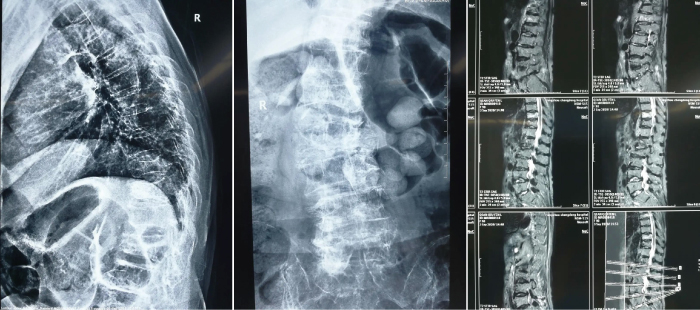

考虑到患者年事已高 , 开放手术和麻醉的风险比较大 。 经过仔细研究、征得家属同意后 , 在我院骨科主任胡睿的带领下 , 决定为钱奶奶行“经皮穿刺椎体后凸成形微创手术” 。 40分钟后 , 手术圆满成功 。 患者术后胸背部及肋腹部的疼痛缓解 , 床上可自由翻身 , 术后第二天可下地自由活动 , 术后一周患者即出院 。

文章图片

(术中)

(术后x片)